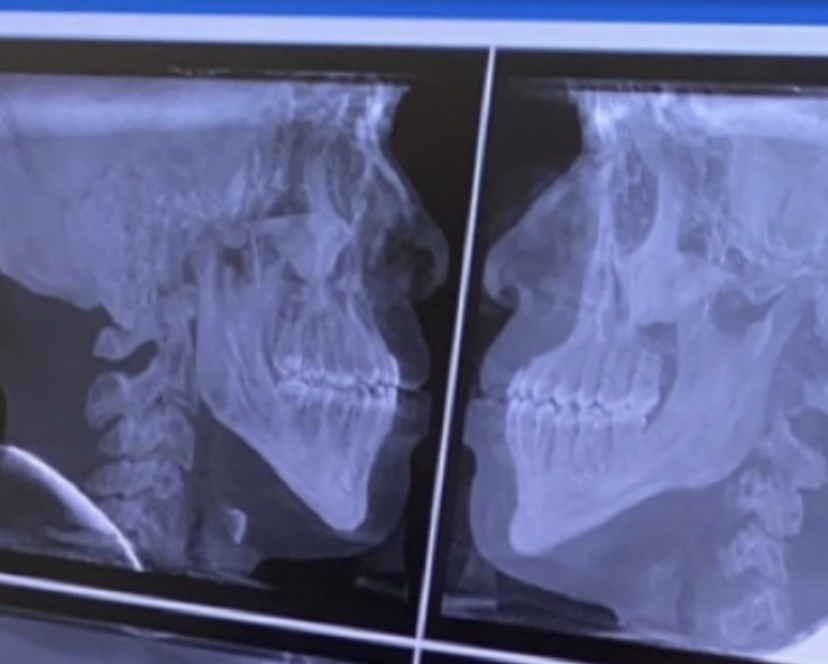

midfacial recessesion often causes mandibular recession and downward growth tho., especially in my case, where my jewish ortho push my forward grown jaw behind my recessed midface instead of making me wear heardgear and cutting my tongue tie.

Now i have a long ass head with no midface and I look boneless

View attachment 1994952